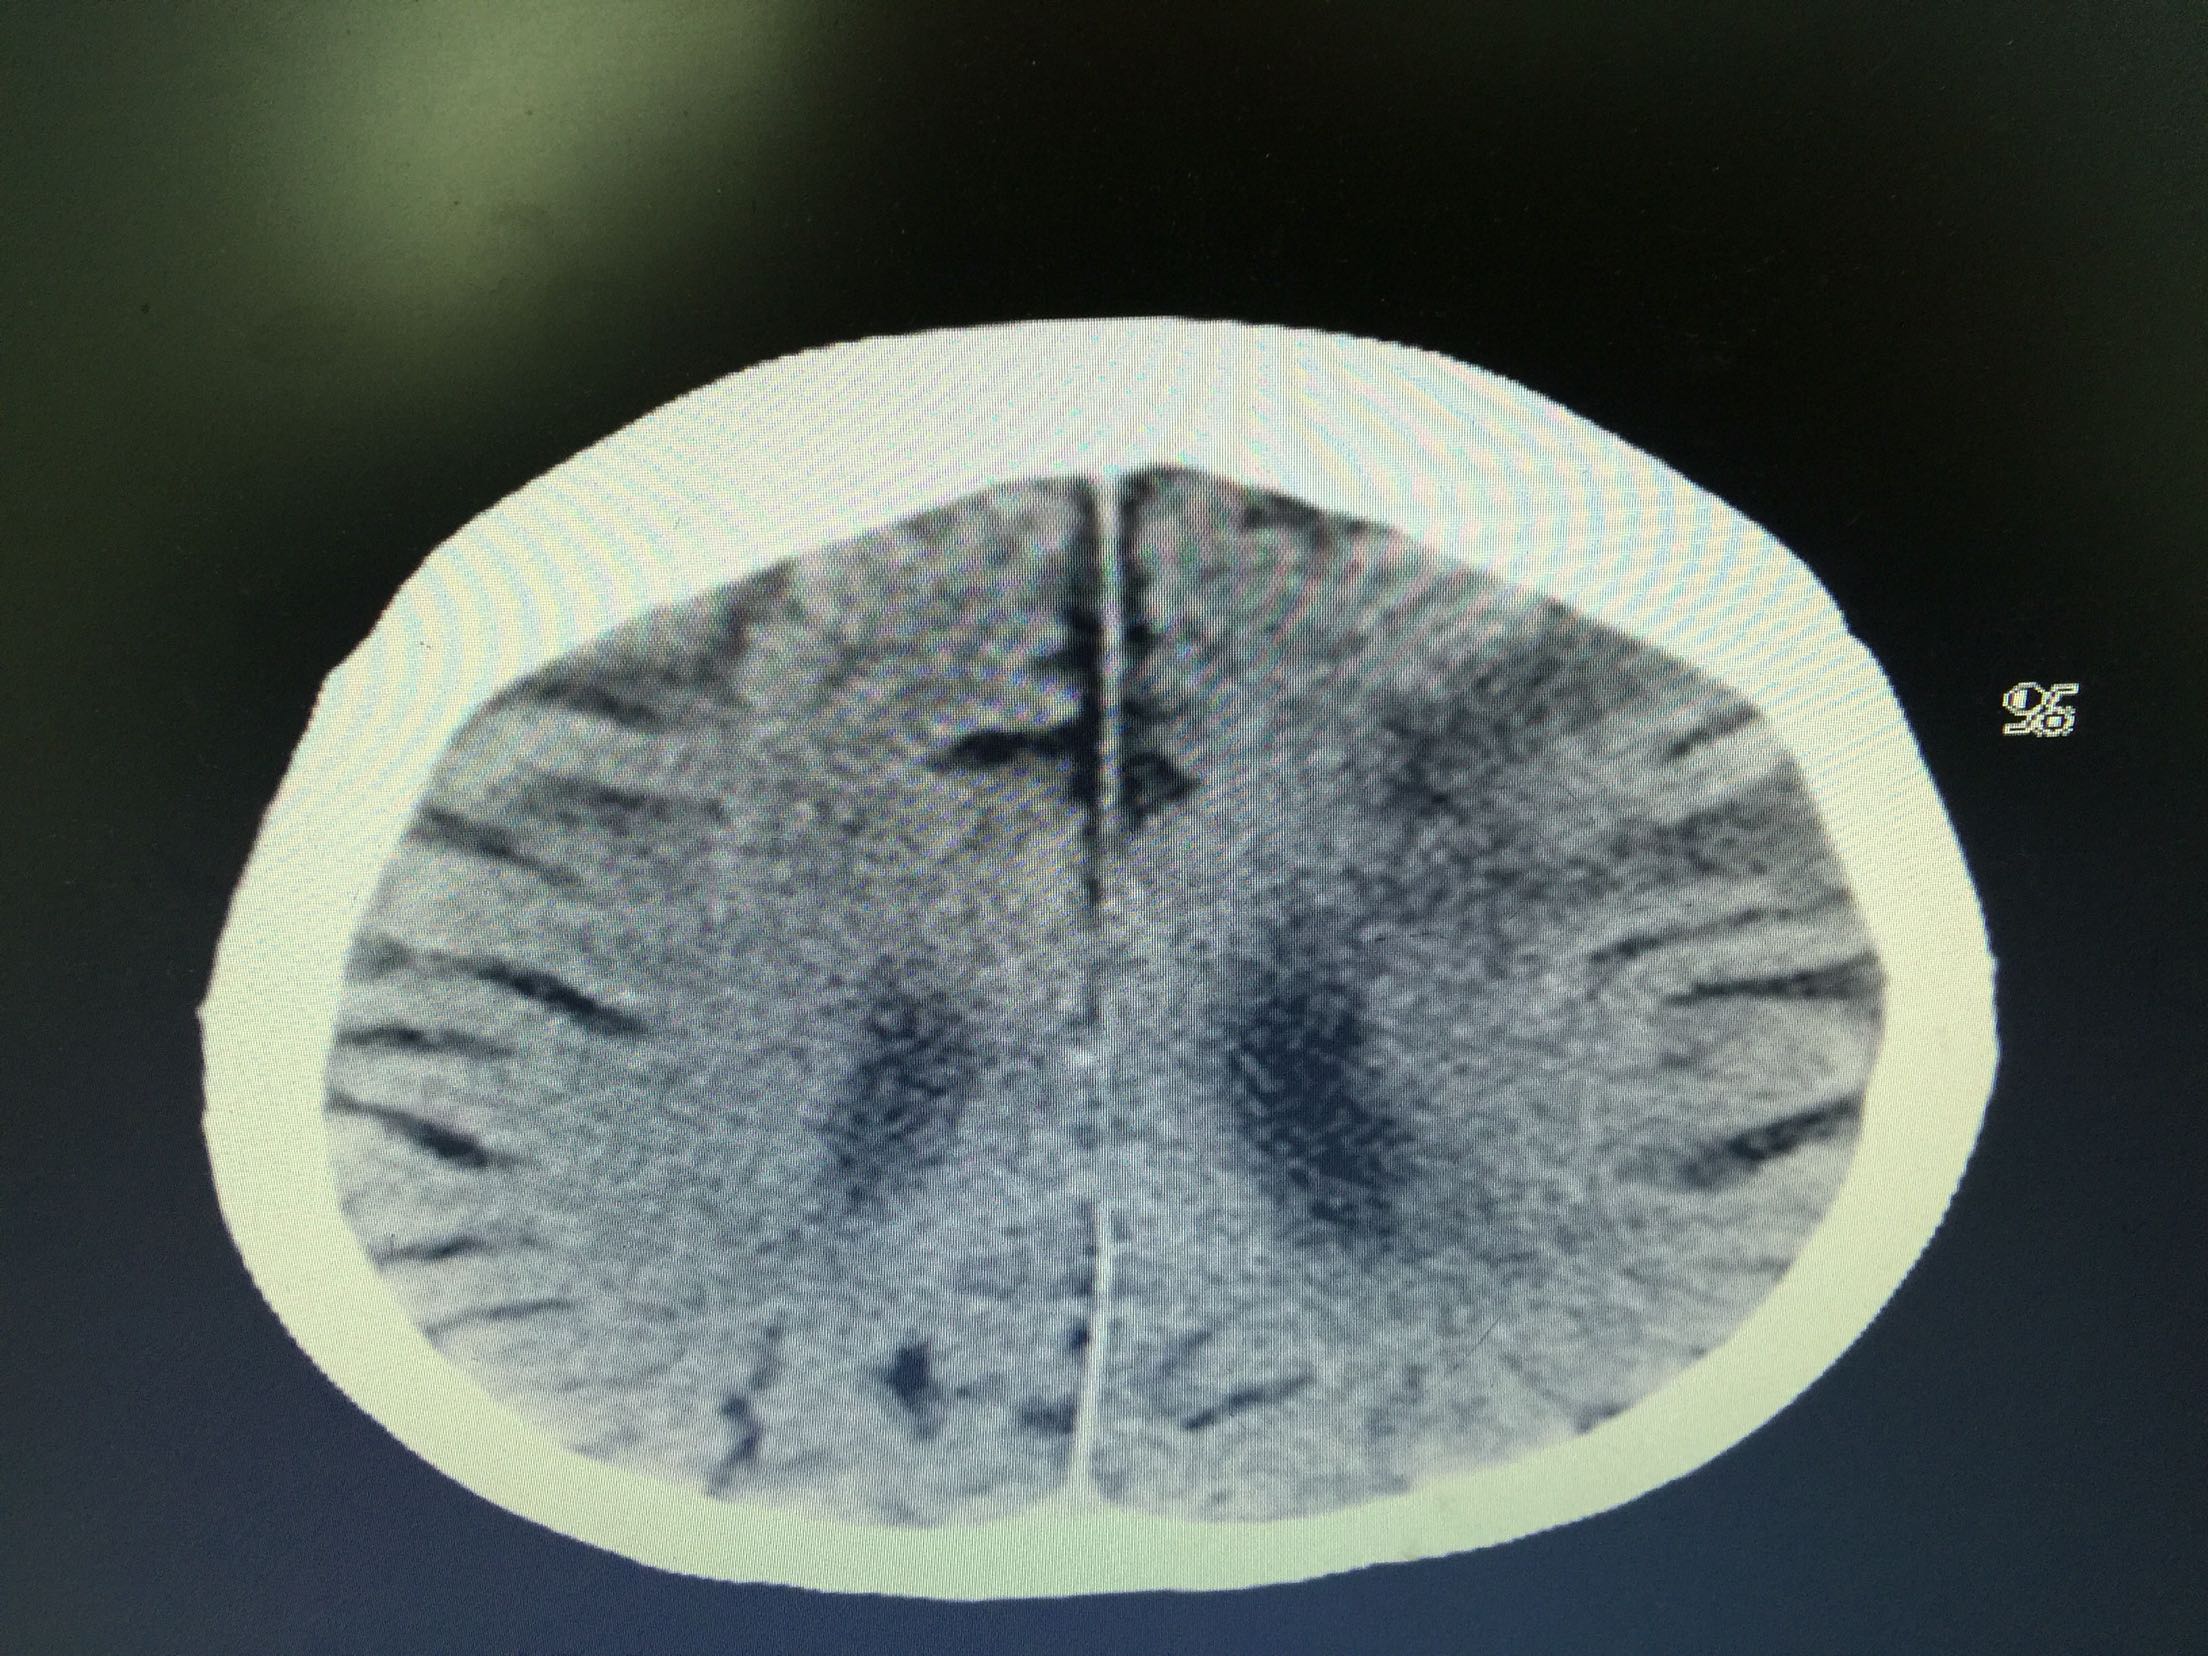

分水岭梗塞1例!

女,86岁,以“嗜睡、右侧肢体无力20小时”入院。 现病史:20小时前无诱因出现嗜睡,可唤醒,问话可答,不理解含义,右侧肢体无力。 既往史:高血压。

查体:血压:136/80mmHg,意识清,不全运动性失语,右侧中枢性面瘫,右侧肢肌力1级,Babinski征左-右+。

诊断:分水岭梗塞! 治疗:扩容、抗板、稳定斑块、促进侧枝建立等治疗。

住院患者,意识障碍较前好转。